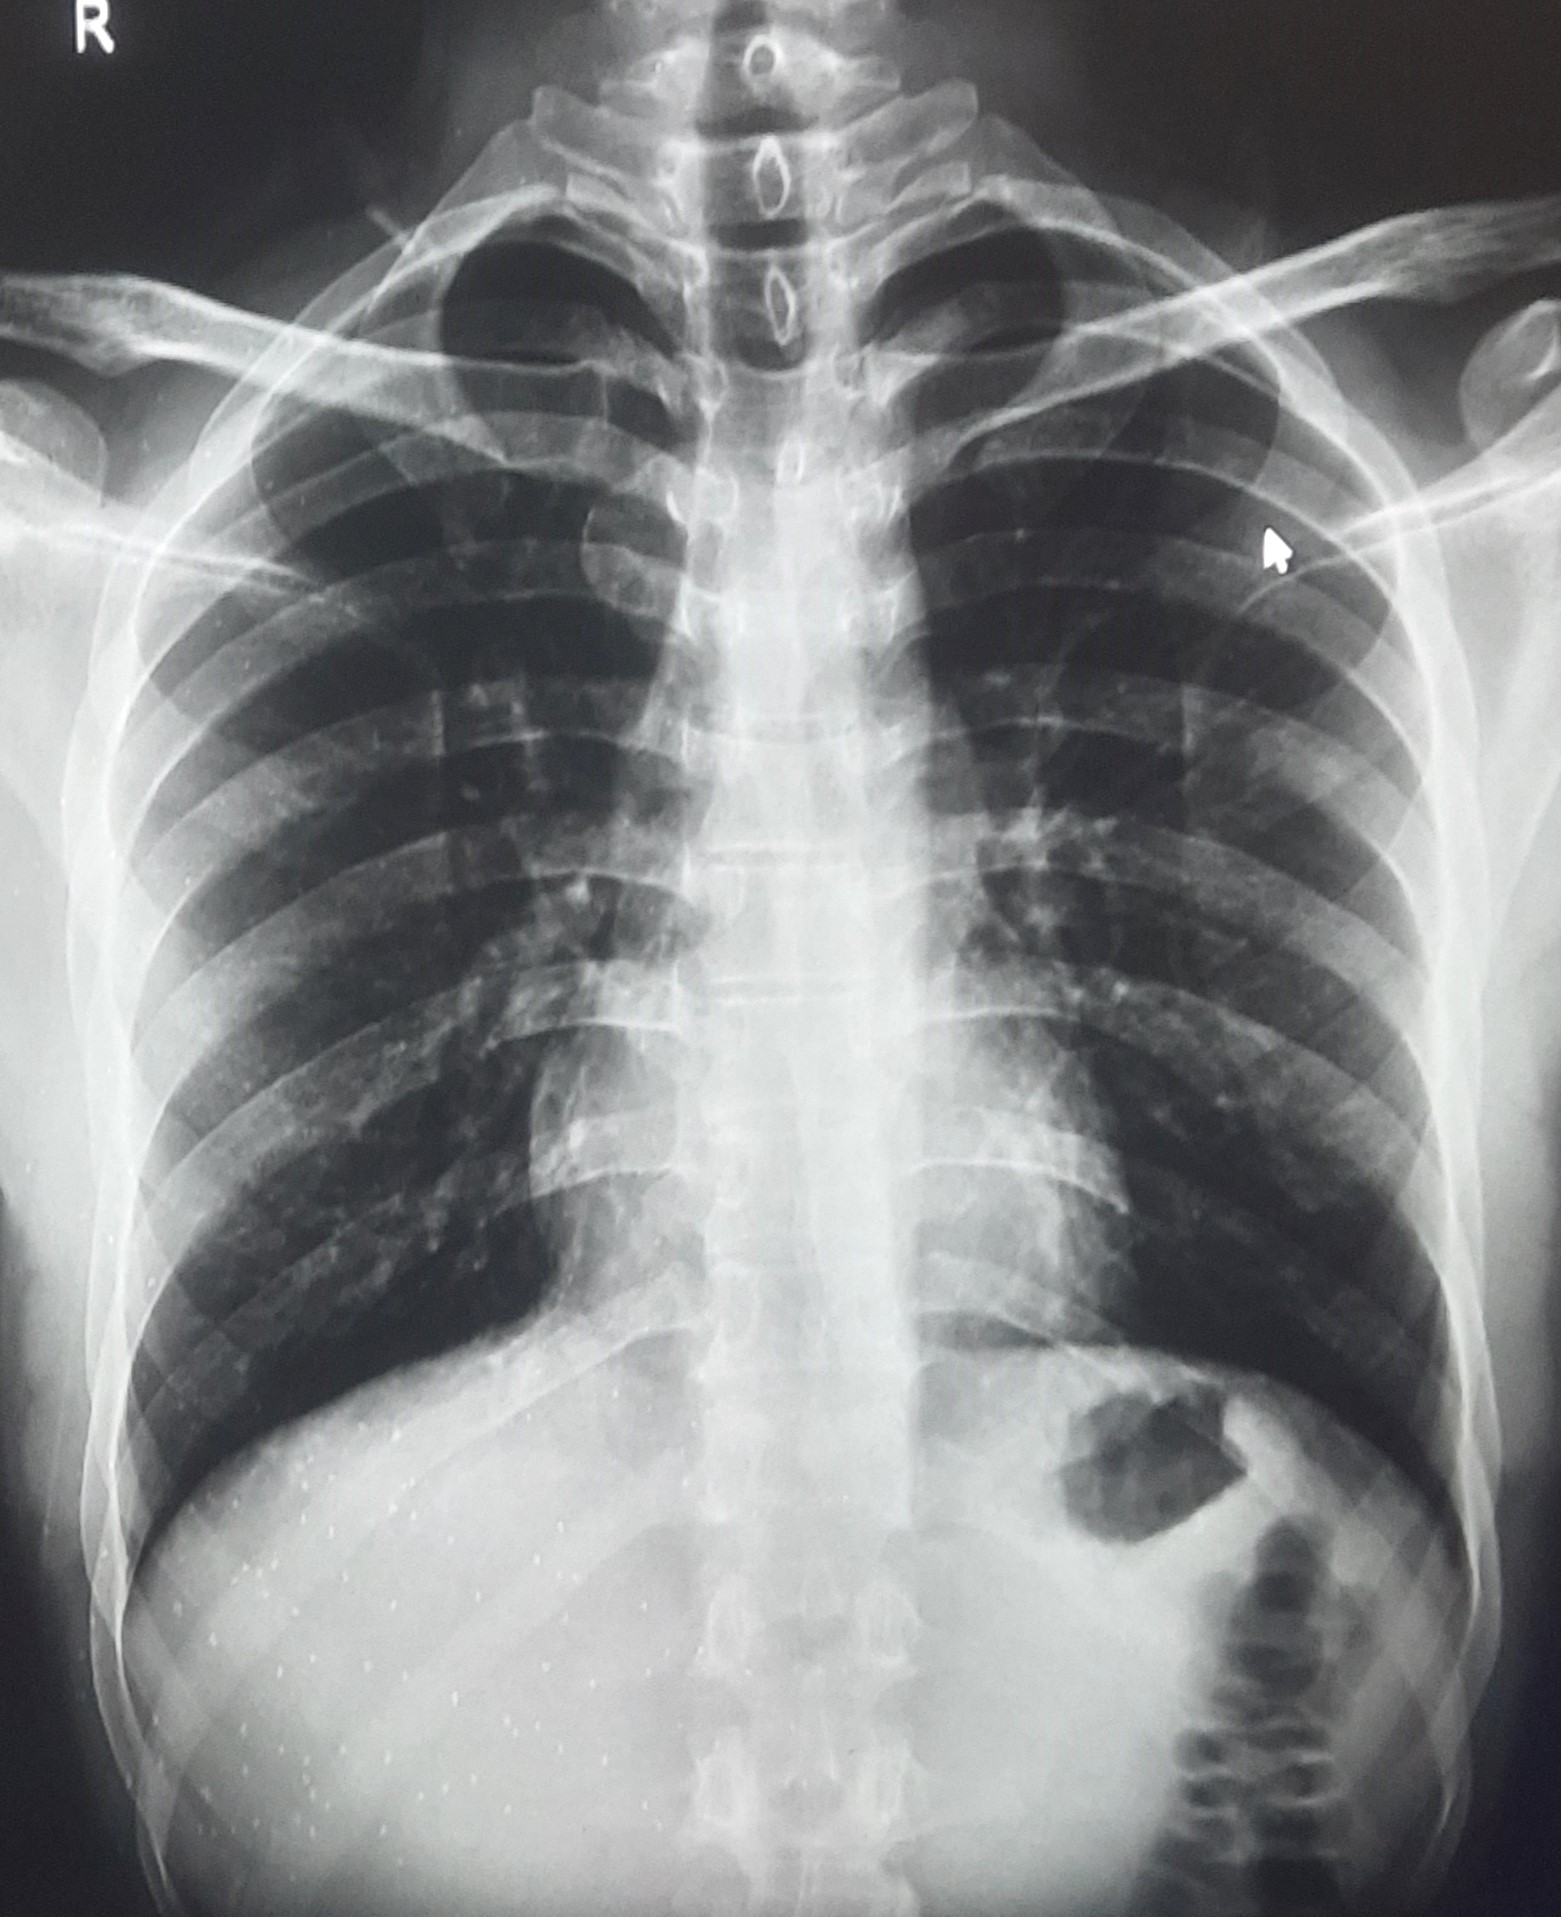

| IGGMC, Nagpur | 29-4197 | IGGMC, Nagpur | Chetan Katare | A/H/O Fall Blunt Trama To Chest 3 Day Ago |

| Chest X-Ray Image |